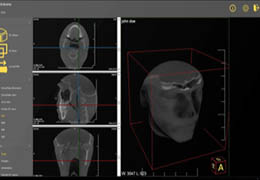

View X-Ray CT & MRI Scans Fast and Easily

FREE and easy to use 3D DICOM Viewer – for surgeons and patient education

Designed for surgeons, Pro Surgical 3D makes it easy to view patient scans quickly. Pro Surgical 3D facilitates the optimal 3D treatment and assessment workflows based on X-ray CT and MRI scans – and best of all, it’s FREE!

Traditional multi-planar slicing

High-quality and fast 3D reconstruction and 3D rendering

Performs 3D reconstruction and volume rendering.

Multi-planar slicing.

Oblique slicing.

Axis-aligned cropping with context.